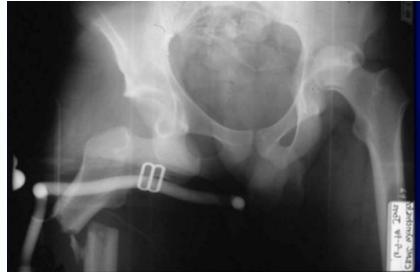

Posterior Hip Dislocation

Clinical Picture:

- Pain, Inability to move hip

- On examination: Limb is short, adducted, internally rotated & slightly flexed

Imaging:

- X-ray & CT scan